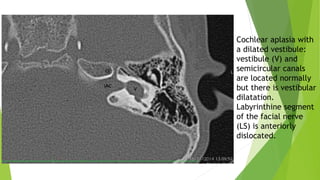

Cochlear aplasia with

a dilated vestibule:

vestibule (V) and

semicircular canals

are located normally

but there is vestibular

dilatation.

Labyrinthine segment

of the facial nerve

(LS) is anteriorly

dislocated.